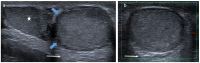

Pre- and post-pubertal testicular tumors are two distinct entities in terms of epidemiology, diagnosis and treatment. Most pre-pubertal tumors are benign; the most frequent are teratomas, and the most common malignant tumors are yolk-sac tumors. Post-pubertal tumors are similar to those found in adults and are more likely to be malignant. Imaging plays a pivotal role in the diagnosis, staging and follow-up. The appearance on ultrasonography (US) is especially helpful to differentiate benign lesions that could be candidates for testis-sparing surgery from malignant ones that require radical orchidectomy. Some specific imaging patterns are described for benign lesions: epidermoid cysts, mature cystic teratomas and Leydig-cell tumors. Benign tumors tend to be well-circumscribed, with decreased Doppler flow on US, but malignancy should be suspected when US shows an inhomogeneous, not-well-described lesion with internal blood flow. Imaging features should always be interpreted in combination with clinical and biological data including serum levels of tumor markers and even intra-operative frozen sections in case of conservative surgery to raise any concerns of malignity. This review provides an overview of imaging features of the most frequent testicular and para-testicular tumor types in children and the value of imaging in disease staging and monitoring children with testicular tumors or risk factors for testicular tumors.